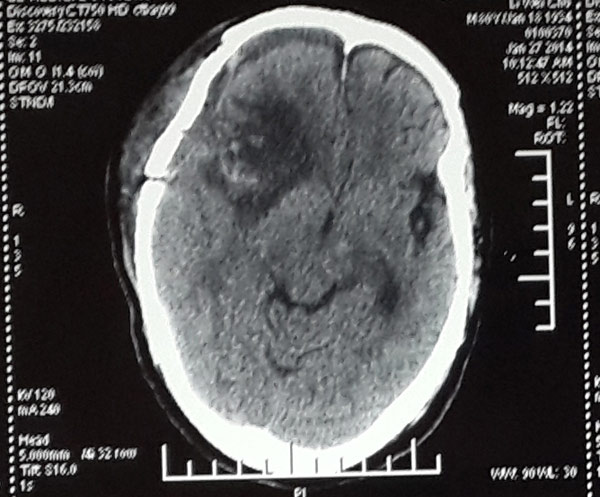

在范学政主任以及张雅轩医生等神经外科医护团队三个多小时的合力奋战,手术顺利完成,脑瘤组织被完全切除,挽救了李大爷的生命。

术后脑膜瘤被完整移除